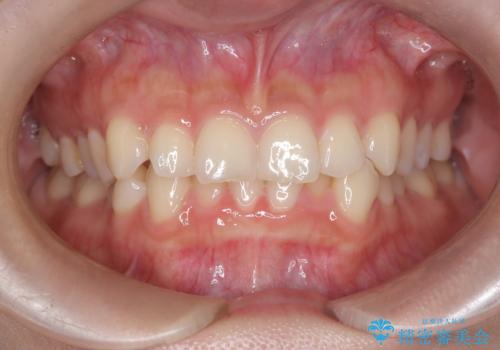

- 前歯のガタガタが気になるとのことでご相談いただきました。診察すると、歯列のスペースが不足し、前歯が重なっている状態でした。抜歯をせずに整えるため、歯と歯の間をわずかに削るIPR(歯列幅径削除)と、奥歯を後方へ動かす遠心移動を組み合わせてスペースを確保しながら並べる治療計画を立てました。

インビザラインを用いて歯を少しずつ移動させながら、IPRで微調整を行い、スペースを確保しました。また、奥歯を遠心移動させることで、前歯を自然な位置に並べることができました。治療後は、「ガタガタがなくなり、スムーズな歯並びになった」と患者様にもご満足いただきました。